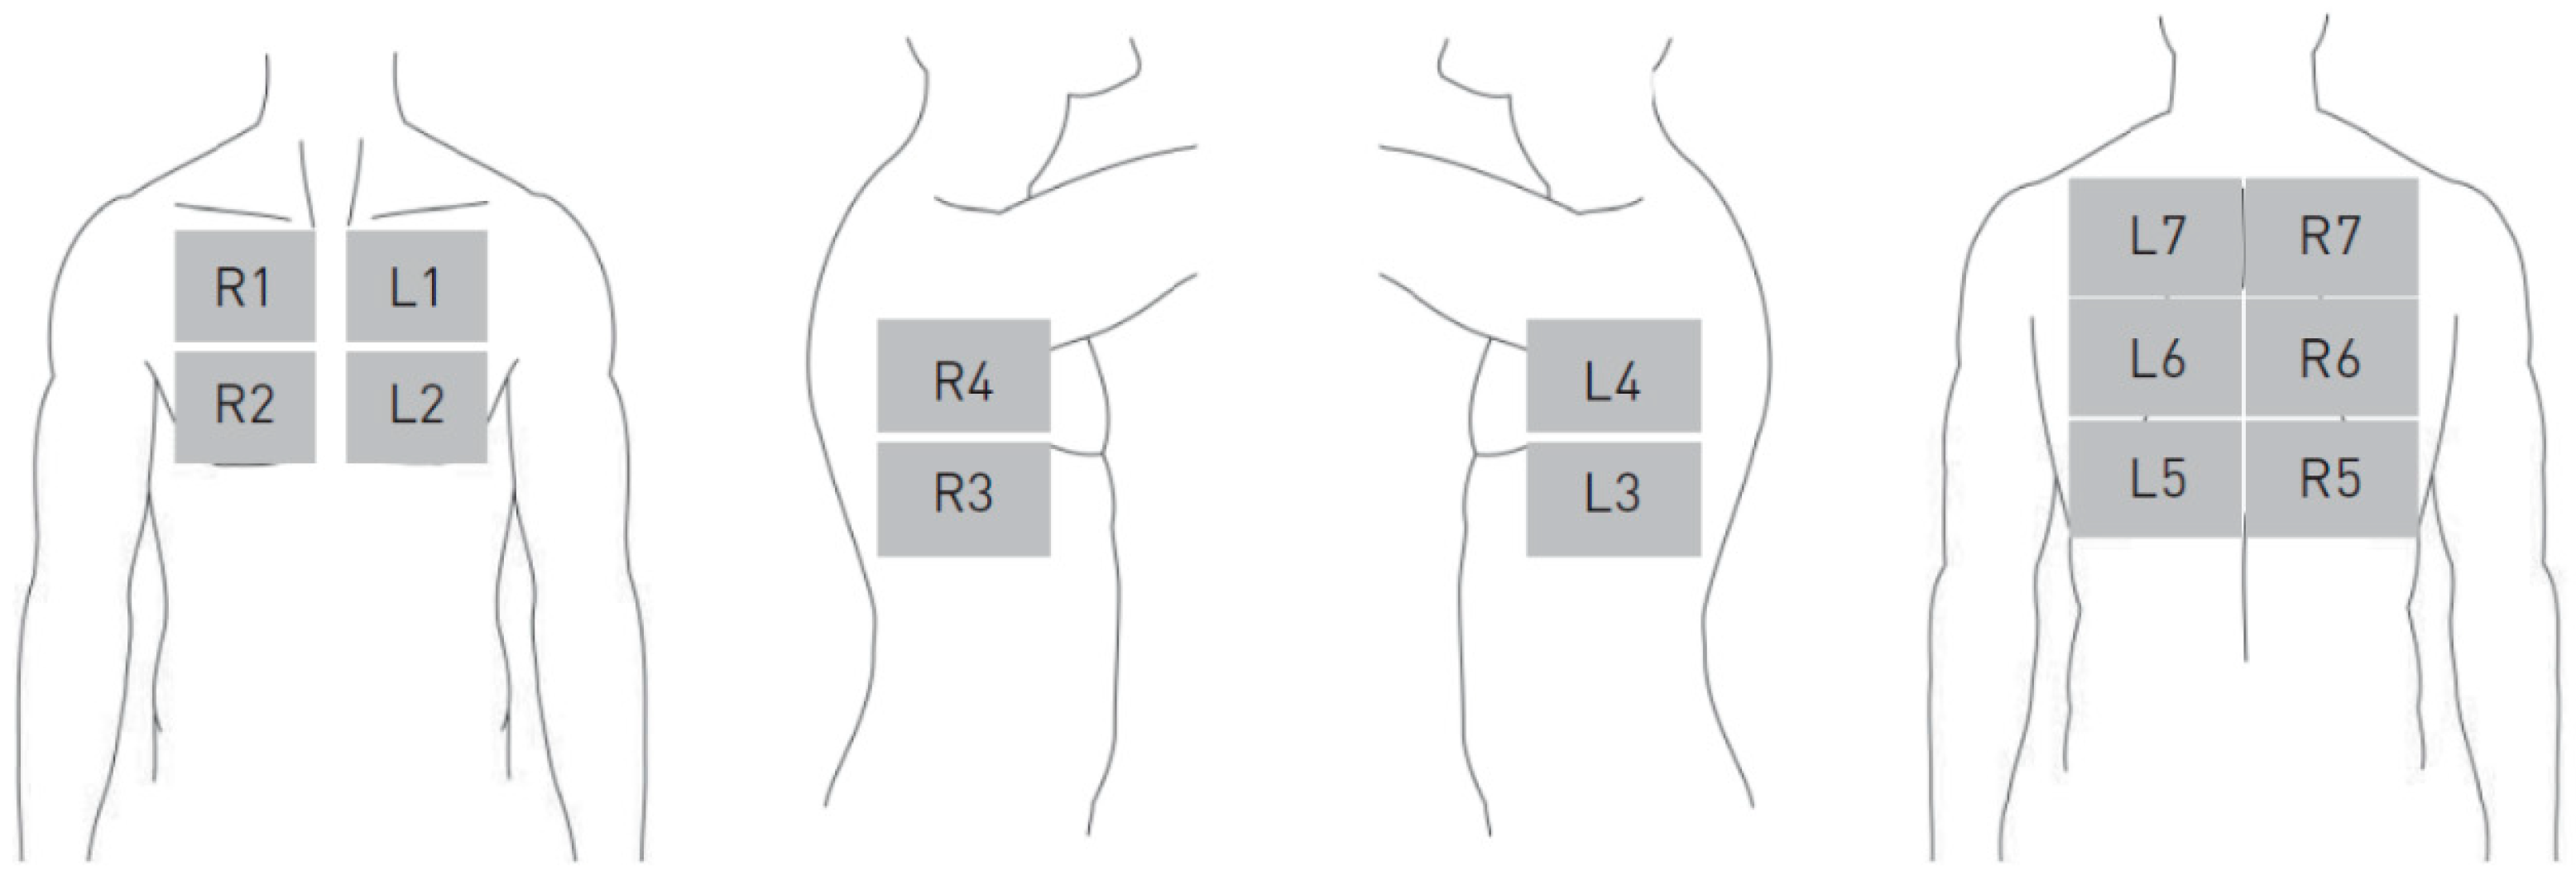

Focused Lung Ultrasound with Integrated Elastography—Procedure